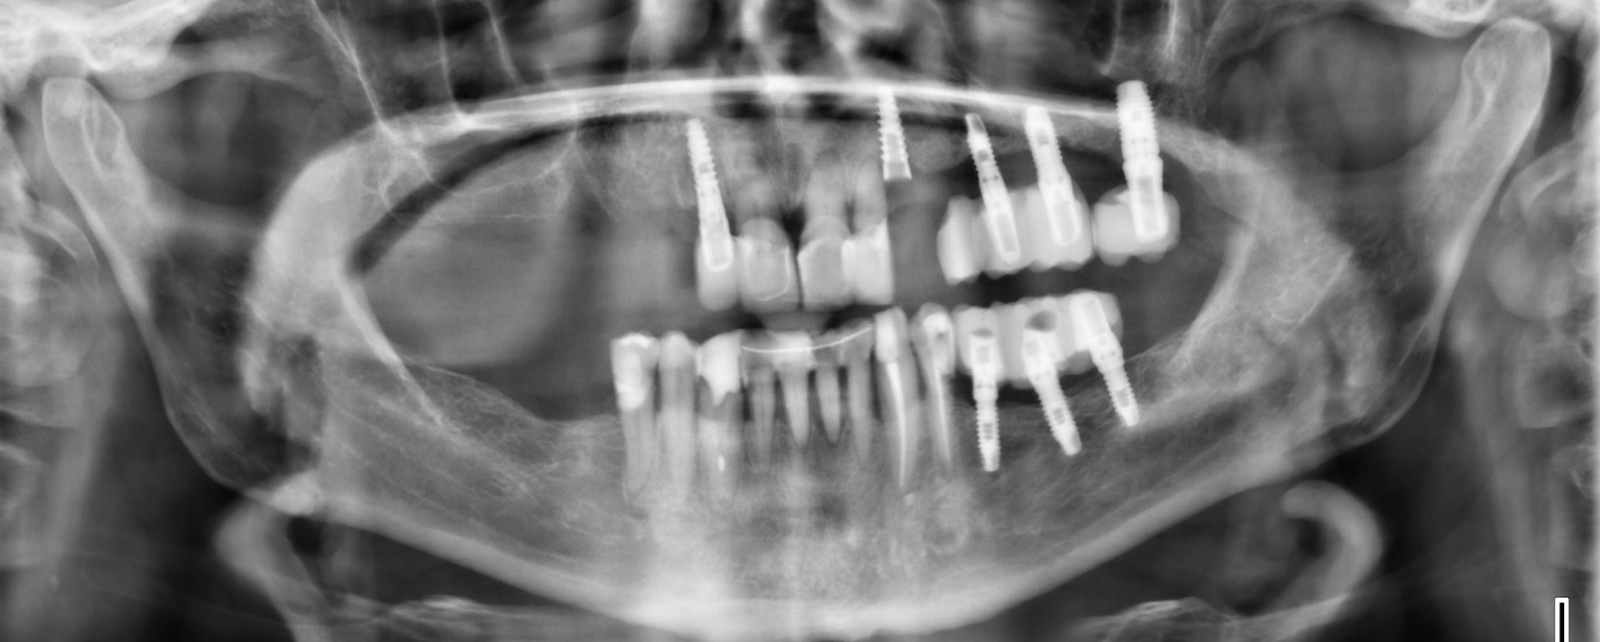

Buenas tardes, Acude a nuestra consulta un paciente para valoración de rehabilitación oral. Hacemos panorámica y presenta estos implantes con pilares para cementar. Necesitamos saber que implantes son los que [...]